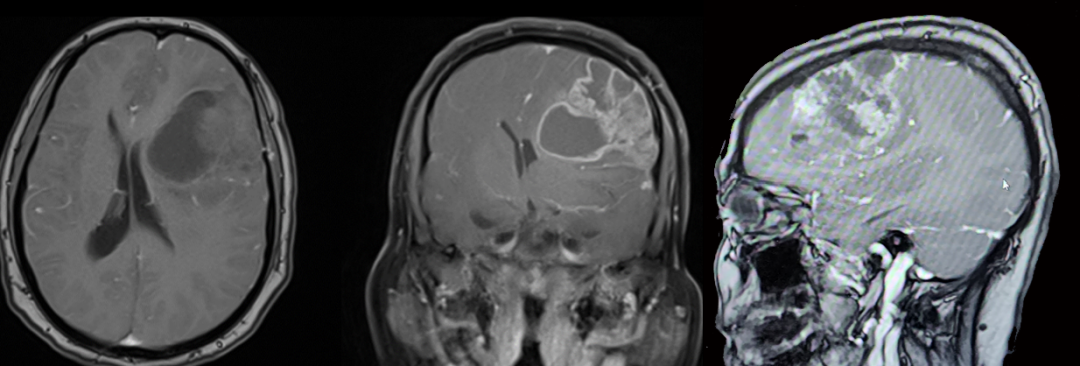

术前MRI:

术后磁共振:

术后患者意识清楚,四肢活动好,对答切题,左眼视力较术前相仿,左侧动眼神经轻度麻痹,进一步康复治疗中。

图30